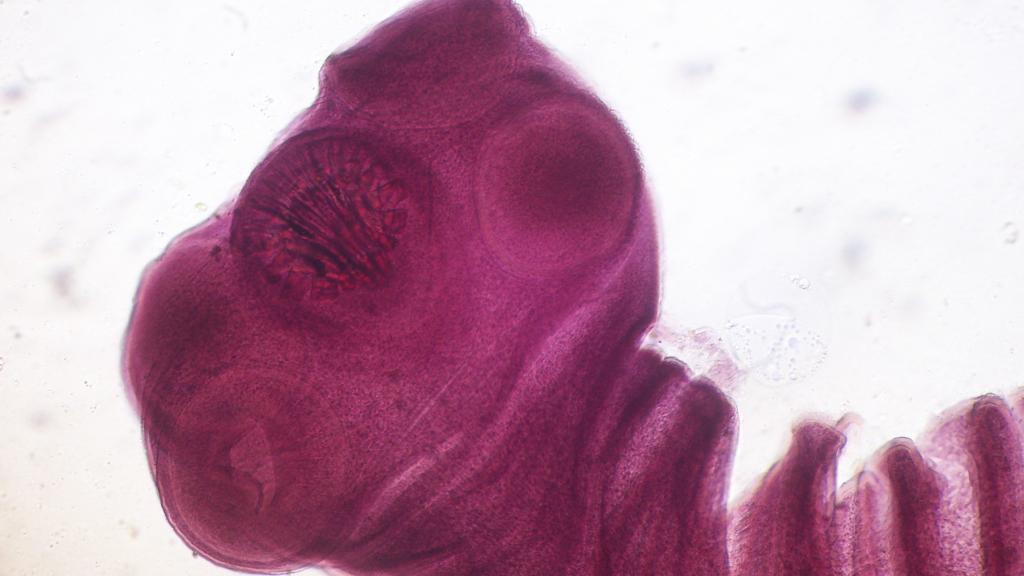

La cabeza del parásito Taenia Solium.

La cabeza del parásito Taenia Solium. Commons.

La cisticercosis es provocada por los quistes larvales de la lombriz Taenia solium, un parásito que se encuentra frecuentemente en el cerdo. Afecta al ser humano cuando ingiere sus huevos a través de suelo contaminado, agua o comida, o incluso por el contacto con otra persona previamente infectada.